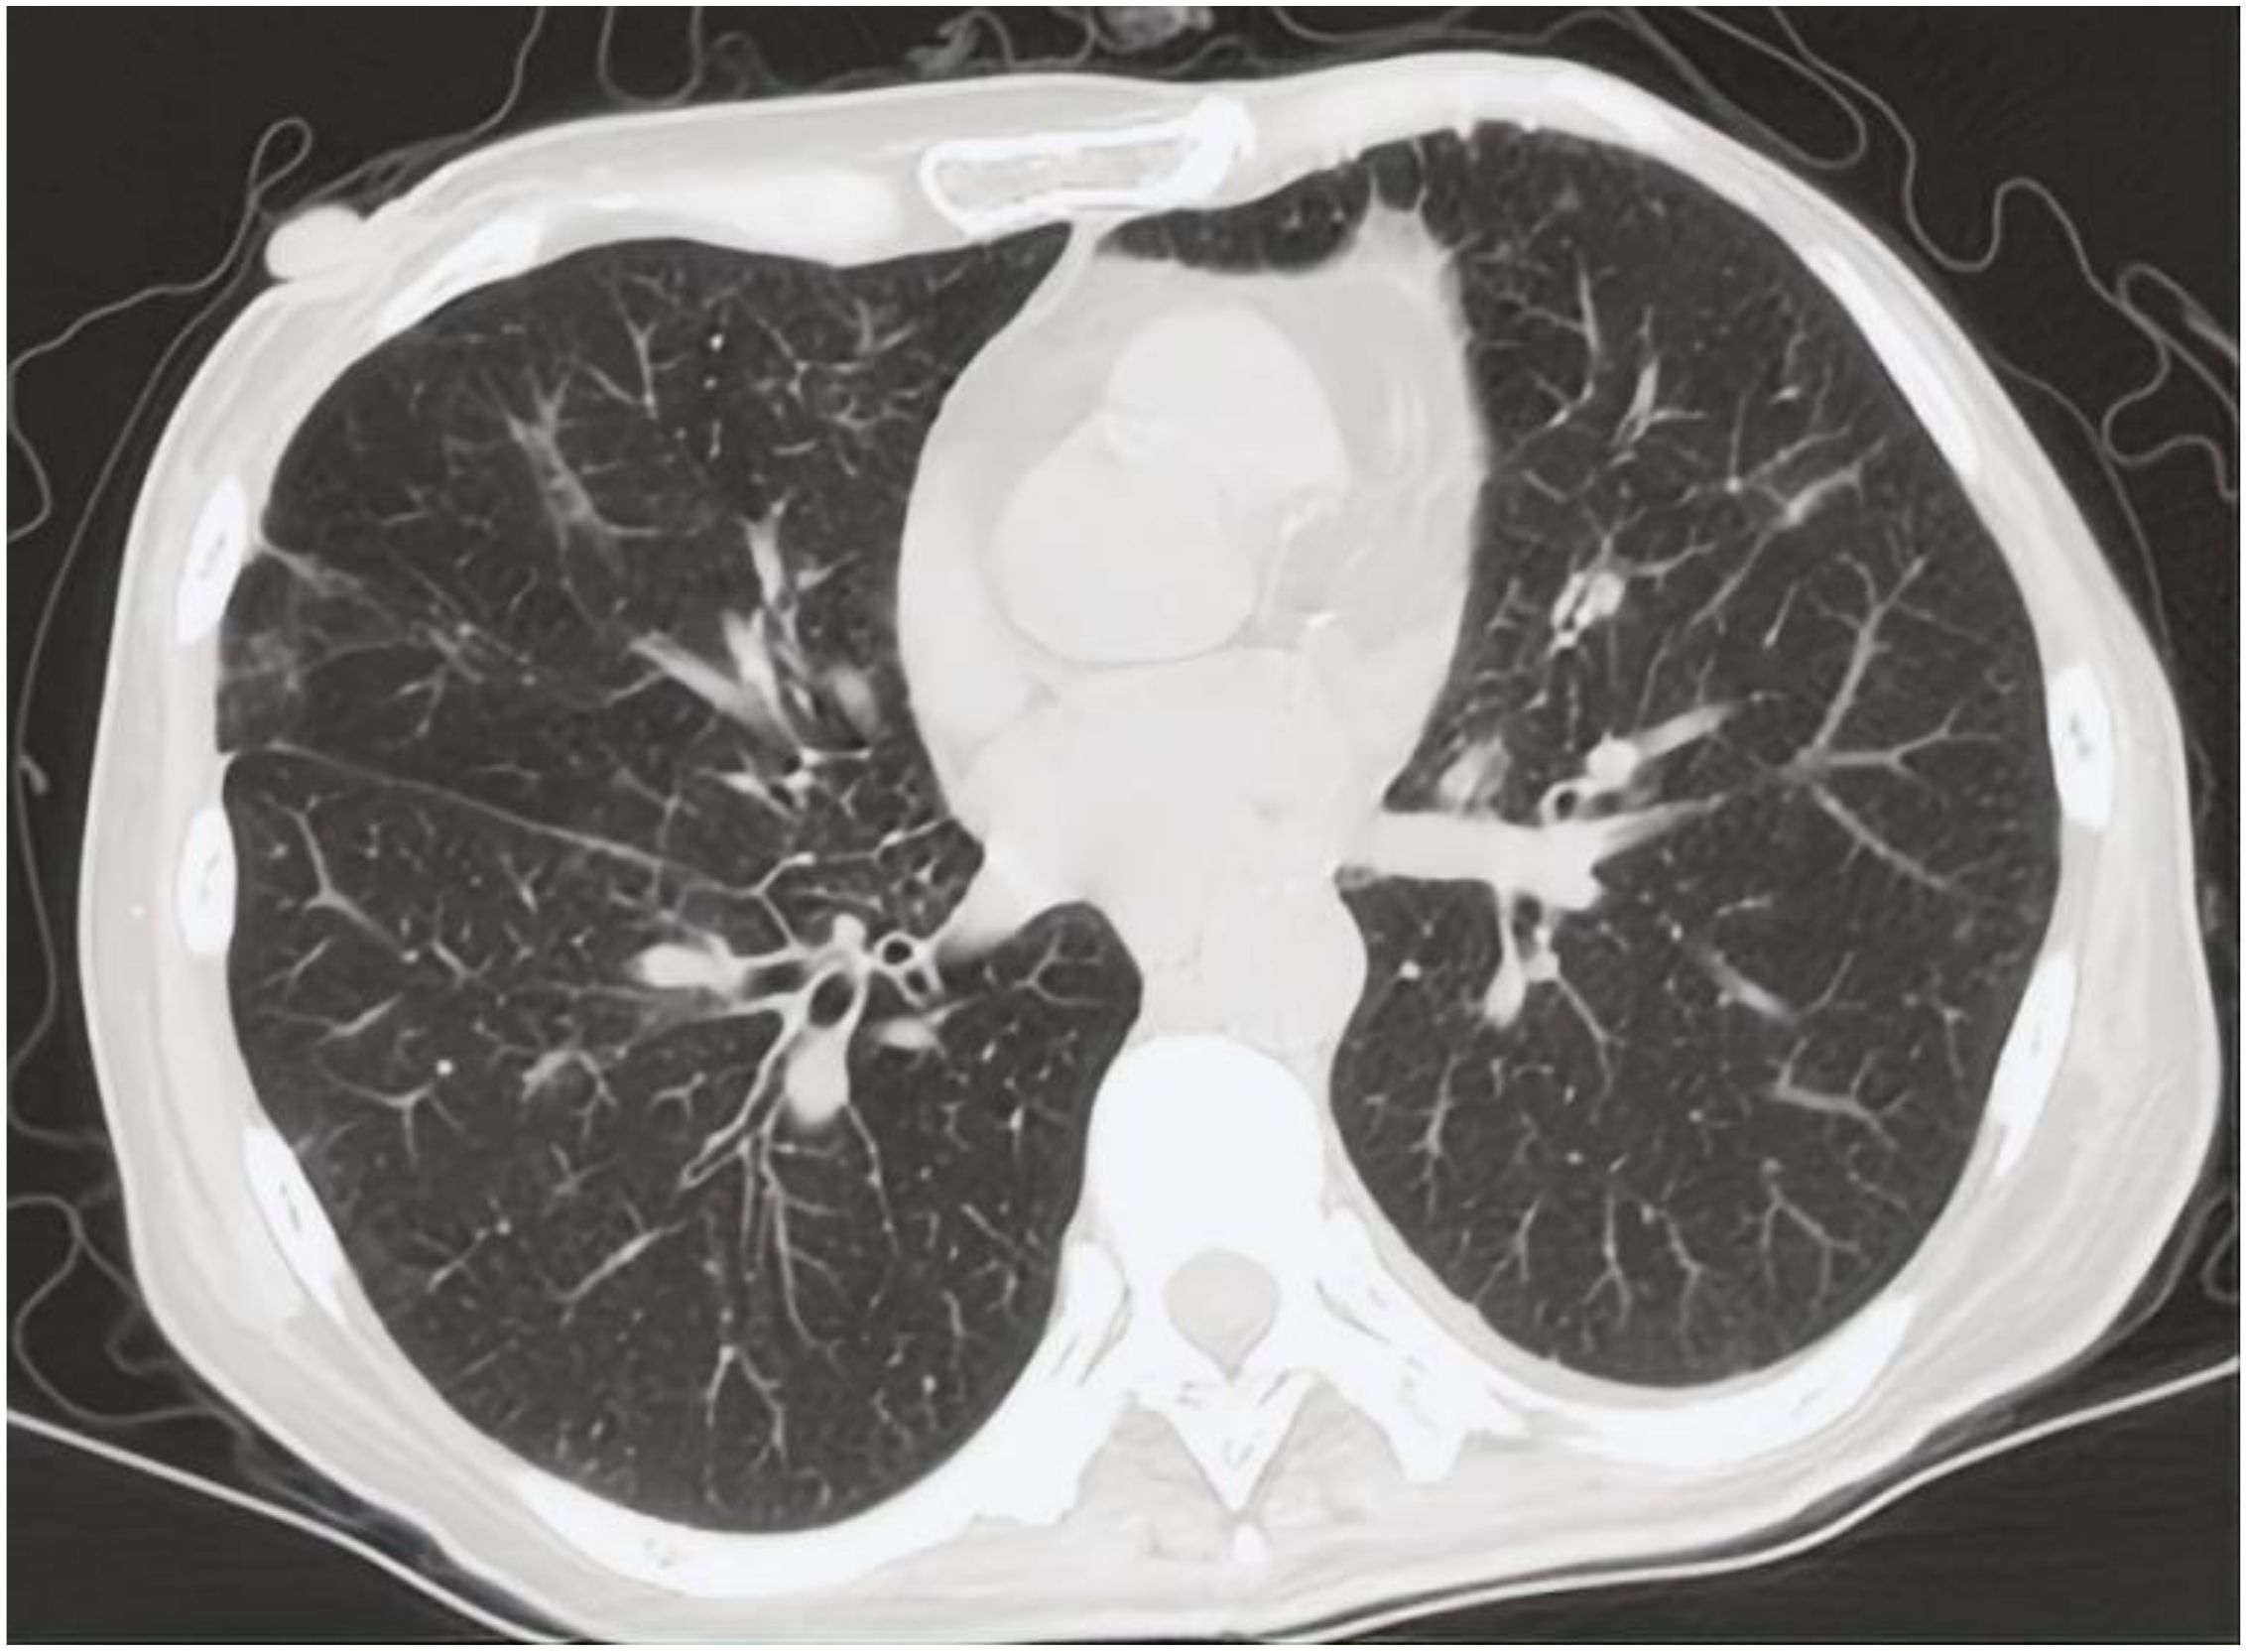

In 2024, a 45kg female patient who was admitted due to fatigue, anorexia, and dark yellow urine for 4 months. Her abdominal distension occurred 4 months ago, and then developed fatigue, loss of appetite, dark yellow urine, and mild abnormal liver function, but she did not take any medical treatment, and these symptoms became worsen in 5 days. 6 years before, she was diagnosed with breast cancer and received surgically resected, multiple rounds of radiotherapy, chemotherapy, and targeted therapy. 4 months before, she was monitored with recurrence of breast cancer and distant metastasis to brain and bones, and begun cranial radiotherapy, meanwhile, the systemic therapies, including targeted therapy, were discontinued. The patient concurrently begun a regimen of anti-tumor Chinese herbal decoctions. She has no family history of liver disease. Physical examination: we found her with severe jaundice of the skin and mucous membranes, and liver palms, and the swelling liver exceeded the right xiphoid 3cm, with a hard texture. Laboratory tests: autoimmune antibodies and serum markers of hepatitis virus were negative. Chest computerized tomography (CT) scan showed multiple small nodules in both lungs, local atelectasis in the right middle lobe and left lower lobe, and postoperative changes were consistent with the loss of the left breast (Figure 1). Suspicious nodules can be seen in some vertebrae, which require further examination. Abdominal CT showed multiple low-density lesions in the liver, ascites, and accessory spleen. MRCP showed that the bile duct in the liver portal area was unclear, which may be due to tumor invasion or external compression, accompanied by uneven expansion of the upper intrahepatic bile duct. (Figure 3).

Figure 1. CT scan of chest showed multiple small nodules considered as metastatic carcinoma in both lungs.